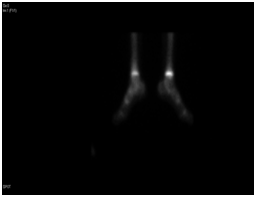

A Saudi girl, 10 years old presented to OPD with progressive swelling of the right ankle for 3 months, localized on the lateral aspect, and increasing with pain and swelling within last two months. During physical examination, proximal area of the skin over the swelling was dark black as what was noted. The patient was investigated primarily in a hospital outside of Riyadh according to a biopsy was taken with osteomyelitis of distal fibula and treatment was start taken but with no response. X-ray of the right leg (Figure 12) and CT of the lower limb (Figure 13). An expansile, lytic and destructive bone lesion is seen involving the distal third of the right fibula. (Figure 14) on MRI showed there is a large destructive bone lesion involving the distal third of the right fibula with sparing of the distal fibular epiphysis. No definite involvement of the right tibia and talus. Trace of fluid is seen in the right tibiotalar joint most likely reactive. The neurovascular structures appear intact. This was followed by technetium-99m MDP scintigraphy (Figure 15), what it showed a solitary focal lesion distal end of right fibula compatible with suspected Ewing's sarcoma. No additional lesions were noted to suggest skip lesions or metastasis. She treated as per Ewing sarcoma protocol in our hospital. Patient was put on neoadjuvant chemotherapy. Later, We did a wide surgical resection of the tumor was preformed upto12 cm from the distal fibula malleolus during which ,the superficial peroneal nerve and peroneus longus and brevis tendon were sacrificed the ruminant of the peroneus longus and calcaneo fibular ligament were sutured and using anchors were attached to the distal tibia in the right leg free pedicle latissmuss dorsi flap was anastomosed to the peroneal artery locally to cover the soft tissue defect by the plastic surgery team. The last MRI done for the patient (Figure 16) showed there is interval reduction in the size of the previously noted heterogeneous enhancing mass at the distal metaphysis of the right fibula. On the bone scan (Figure 17), there is interval reduction in the size of the previously noted heterogeneous enhancing mass at the distal metaphysis of the right fibula. There is no sign of skip metastases to other limb. Bilaterally bone marrow signal changes are most likely related to chemotherapy. The patient will follow up with us regularly.